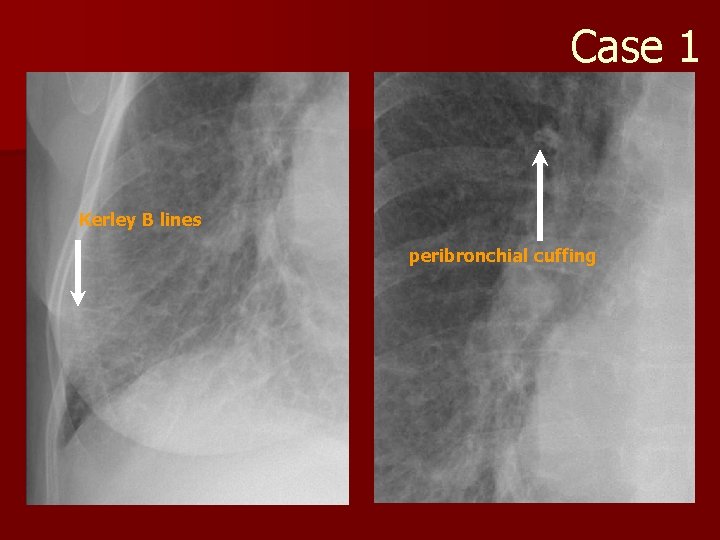

Case 1 Kerley B lines peribronchial cuffing

Pulmonary edema n Radiographic (5) signs of pulmonary edema? – Enlarged cardiac silhouette – Kerley B lines (fluid in the interlobular septae) – Peribronchial cuffing – Indistinctness of the pulmonary vessels – Pleural effusion